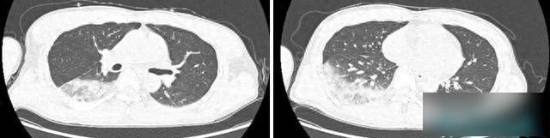

最终,家人送其就诊检查显示,系列检查结果出来后,让所有人都大吃一惊:林师傅不仅双肺下叶出现炎症,肝功能、肾功能也受到了损伤,多项炎症指标更是大幅超出正常范围。